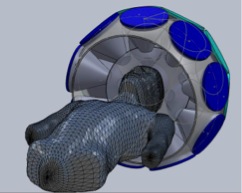

The third example of our current investigations is the development of a multi-detector-module multi-pinhole (MPH) SPECT brain-imaging system ideally suited for quantitative dynamic and high-spatial-resolution static SPECT imaging. Dynamic imaging will be enabled by obtaining sufficient angular sampling without the need for rotation. The system will automatically adapt its imaging characteristics (aperture size and number of pinholes open for imaging) in response to the imaging tasks and individual patients. It will thereby optimize lesion detection and quantification, as well as provide optimal data for pharmacokinetic analysis within structures throughout the brain. The prototype design for this system is illustrated in the following computer aided design (CAD) drawings. These investigations are funded by NIH grant R01-EB022521.

|

|

| Shown left is a frontal view and right is a view from behind of SolidWorks CAD renderings of the proposed prototype configuration of the 23 detectors of the system dedicated to brain SPECT imaging. Shown are detector modules with MPH aperture plates towards the brain and circular scintillation detector crystals opposed to them. | |